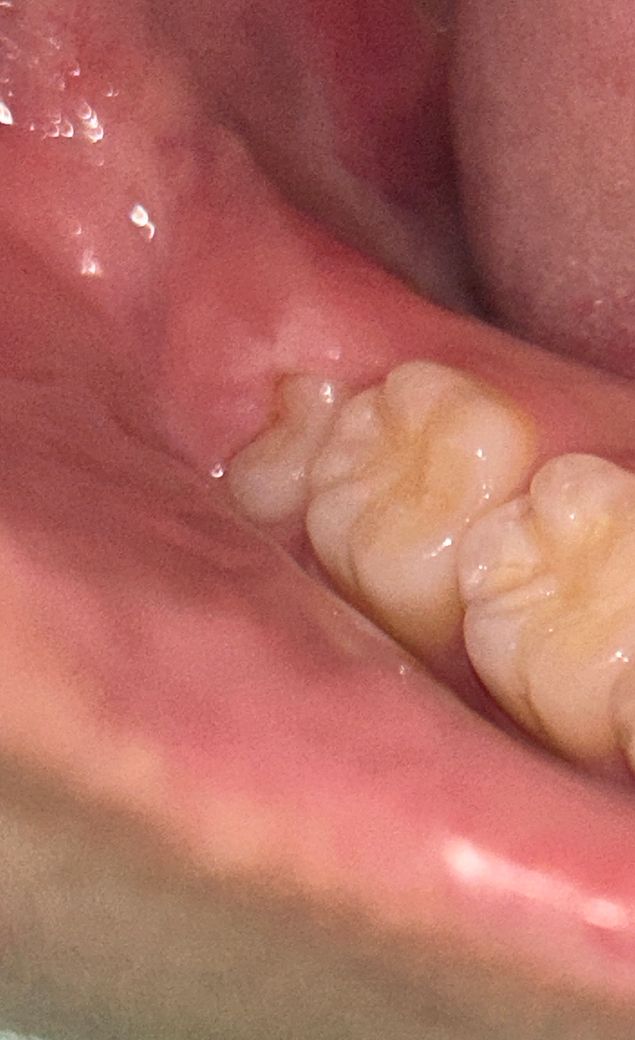

반만 나온 사랑니는 무조건 빼야할까요? ㅠㅠ..

• 양쪽 아랫 사랑니 방향이 올바르게 난건가요?

양 쪽 아랫 사랑니

• 2번 째 사진

사진으로 봤을 경우 치아는 정상적으로 올라오고 있는것으로 보입니다.

사랑니라고 해도 정상적으로 맹출이 되어 있다면 관리를 하면서 사용할수 있습니다.

사랑니가 지금처럼 난 경우에는 관리가 어려워 추후 문제가 될 수 잇습니다. 빼는 게 좋겠습니다.

지금은 어느정도 관리가 되고 잇지만 잇몸사이에 음식물이 들어가면서 관리가 안되면 염증이 자주 생길수 있습니다. 발치를 하시는게 좋을것같습니다.

현재 사랑니 방향이 비뚫어 나오는 것으로 보이며, 이 경우 앞의 어금니에 영향을 미칠수 있습니다. 따라서 인접 치아를 보호하기 위해서라도 발치를 하길 권장드립니다.